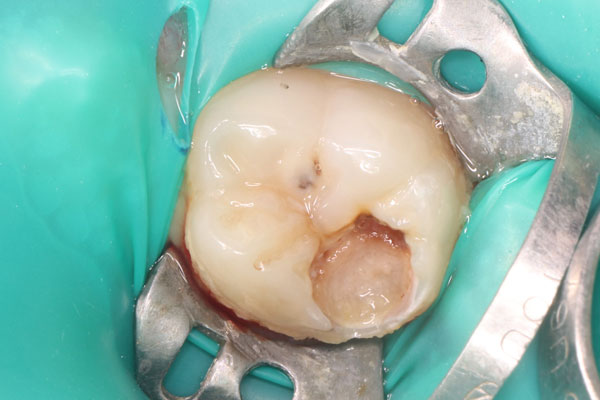

Лечение под микроскопом: фото До и После